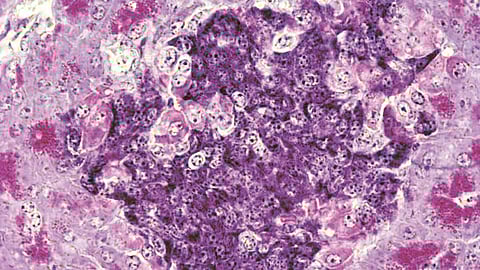

‘टाईप 1’ मधुमेहामध्ये शरीराची रोगप्रतिकारकशक्ती चुकून इन्सुलिन तयार करणार्या पेशींवरच हल्ला करते आणि त्या नष्ट करते. आतापर्यंत यावर उपाय म्हणून दात्याकडून मिळणार्या पेशींचे प्रत्यारोपण केले जात असे. मात्र, शरीर या नवीन पेशी स्वीकारण्यासाठी रुग्णाला आयुष्यभर अत्यंत कडक ‘इम्युनोसप्रेसंट’ औषधे घ्यावी लागत. या औषधांच्या दुष्परिणामांमुळे अशा प्रत्यारोपणाचा वापर मर्यादित होता. नुकत्याच झालेल्या एका संशोधनात संशोधकांनी ‘कायमेरिक’ किंवा ‘मिश्र’ रोगप्रतिकार यंत्रणा विकसित केली आहे.

यामध्ये रुग्ण आणि दाता या दोघांच्याही रोगप्रतिकार यंत्रणेचे घटक एकत्र करण्यात आले. यामुळे उंदरांच्या शरीराने कोणत्याही दीर्घकालीन औषधांशिवाय इन्सुलिन तयार करणार्या नवीन पेशींचा स्वीकार केला. वॉशिंग्टन युनिव्हर्सिटीतील तज्ज्ञ डॉ. जॉन डिपेर्सिओ यांच्या मते, ‘हा मधुमेहावर कायमस्वरूपी उपचार करण्याचा एक संभाव्य मार्ग आहे. सैद्धांतिकद़ृष्ट्या हे एक खूप मोठे पाऊल आहे.’ संशोधकांनी एकाच दात्याकडून मिळणार्या ‘अस्थिमज्जा स्टेम सेल्स’ आणि ‘आयलेट सेल्स’ यांचा वापर केला. या प्रक्रियेत स्टेम सेल्स शरीरात गेल्यावर पांढर्या पेशींची पुन्हा निर्मिती करतात.

ही नवीन विकसित झालेली रोगप्रतिकार यंत्रणा जुन्या दोषांना (इन्सुलिन पेशींवर हल्ला करणे) विसरते आणि नवीन प्रत्यारोपित केलेल्या पेशींना स्वतःचाच भाग म्हणून ओळखते. यामुळे शरीर त्या पेशींना नष्ट करत नाही. जरी उंदरांवरील हे प्रयोग यशस्वी झाले असले, तरी मानवावर उपचार करण्यापूर्वी अजून बराच काळ संशोधनाची गरज आहे. मिश्र रोगप्रतिकार यंत्रणेमध्ये संतुलन राखणे हे मोठे आव्हान आहे. परंतु, जर मानवी चाचण्यांमध्ये हे तंत्रज्ञान सुरक्षित आणि टिकाऊ आढळले, तर हृदयविकार, किडनीचे आजार आणि डोळ्यांचे नुकसान करणार्या या जीवघेण्या मधुमेहावर कायमचा तोडगा निघू शकेल.